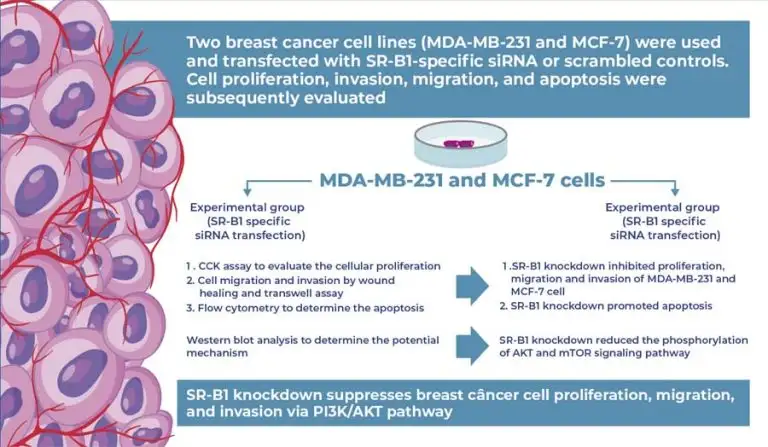

Highlights ■ SR-B1 knockdown inhibits breast cancer cell proliferation and migration. ■ Silencing SR-B1 promotes apoptosis in breast cancer cells. ■ PI3K/AKT pathway activity decreases after SR-B1 knockdown. ■ Cyclin D1 and P70 are downregulated following SR-B1 silencing. ABSTRACT Background: The role of scavenger receptor class B type 1 (SR-B1) in breast cancer remains largely unknown. Objective: This study aimed to investigate the effects of SR-B1 on breast cancer cell proliferation, migration, and invasion and to elucidate the underlying mechanisms. […]